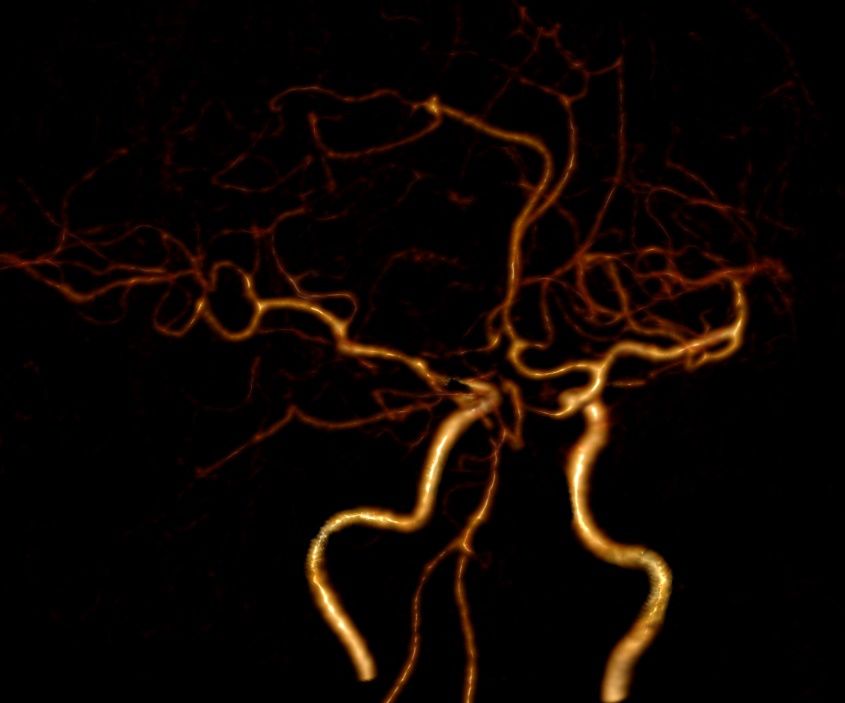

术前外院DSA提示:左侧颈内动脉后交通动脉瘤呈不规则腊肠形,约4*10mm,右侧小脑上动脉瘤呈球形,约3*4mm,胼周动脉瘤,约2*3mm。

图1-1. 外院头颅DSA结果提示颅内多发动脉瘤:分别为左侧颈内后交通动脉瘤、右侧小脑上动脉瘤、胼周动脉瘤。